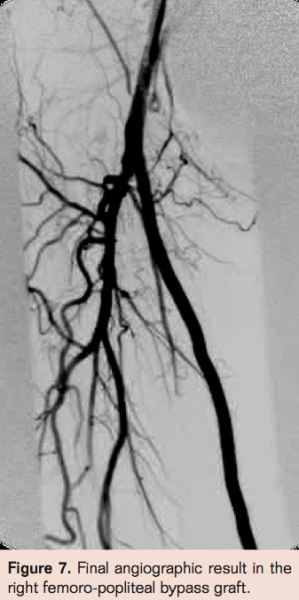

- Laser thrombectomy at 1 mm/sec. with the 2.3 mm probe (Figures 4-9)

Findings

Complete angiographic resolution of thrombus and definitive therapy was achieved in 51 of 78 patients (65.3%) during the index angiographic procedure in the angiographic suite. In 12 of 78 patients (15.3%) flow was established in the index procedure but there was residual thrombus necessitating continued lytic infusion. Of those 12 who had residual thrombus, 11 had complete resolution of thrombus following 3 hours of lytic therapy allowing definitive therapy in the same day. No flow was established during the index procedure for 15 of 78 patients (19.2%). Of these patients angiography via the side hole perfusion catheter showed substantial resolution of thrombus but enough residual thrombus to obstruct antegrade flow in 14 of 15. There was no evidence of thrombus resolution in 1 of 15 patients for whom no flow was established in the index procedure. Of those 15 patients,3 (20%) had complete resolution of thrombus at 3 hours post angiography while 12 of 15 patients (80%) required prolonged lytic infusion. Graft patency was established in 78 of 78 patients but bleeding complications were much less common in the group with successful index procedure than those requiring overnight infusion (2% vs 47% with major bleeding necessitating transfusion of 2 units of PRBC’s in 2 patients who had overnight lytics).